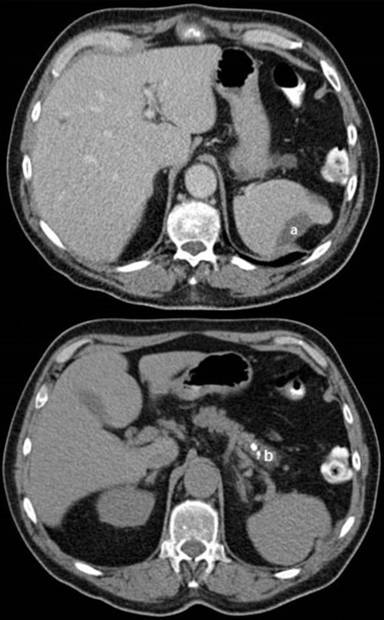

Follow-up laboratory investigations at 2 months revealed that his lipase, amylase and serum IgG4 levels had normalised. Follow up CT-scans of the abdomen at 2 and 6 months (Figure 2) showed the pancreatic pseudocyst had resolved and the splenic haemorrhage had reduced in size to 39x15 mm. In view of these findings, his steroid dose was tapered and completely stopped after a total of 4 months. The patient was followed up in the outpatient clinic for a further 6 months during which time he remained well with no relapse of his autoimmune pancreatitis.

Figure 2. CT scan at 6 months. Improvement in the size of the splenic haemorrhage (a.) to 39x15 mm and resolution of the pancreatic pseudocyst and pancreatic calcification (b.) |